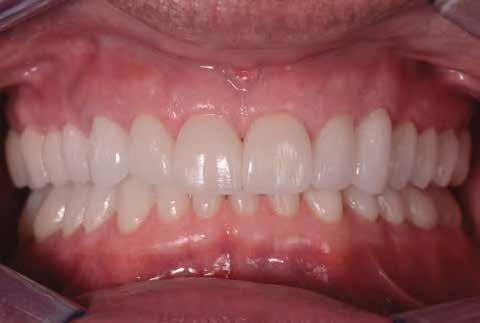

Dr. Marco Nicastro (Olaszország) A kiindulási állapot és a végeredmény. A KATANA™ UTML kiváló esztétikai tulajdonságokkal rendelkezik, és tökéletesen, harmonikusan illeszkedik a rózsaszín szövetekkel.

1. ábra: A beteg esztétikai problémájára kért megoldást a régi restaurációk természetellenes megjelenése, továbbá a múltban lezajlott periodontitis következtében kialakult fekete háromszögek miatt. A szövetek visszahúzódása következtében a fogpótlás széle jól láthatóvá vált, a papilla csúcsok elvesztése és a koronák közötti számos fekete térrel együtt, komplex terápiás ellátást igényelt.

16. ábra: Klinikai fotó egy évvel a PANAVIA V5-tel történő beragasztás után. A marginális szövetek jó klinikai állapotát látjuk, semmi jele gyulladásnak vagy vérzésnek. A BOPT lehetővé teszi számunkra, hogy optimalizáljuk a gingiva szintjét anélkül, hogy parodontológiai sebészeti beavatkozáshoz folyamodnánk, miközben az új koronák alakja lehetővé tette az interproximális terek zárását az optimális esztétikai eredmény érdekében.

17. ábra: A fogpótlás világossága (főleg a transzlucentes cirkónium használatának köszönhetően), a metszők alakjával kombinálva nagymértékben javította a pótlás esztétikáját, még akkor is, ha a kiindulási helyzet különösen kedvezőtlennek tűnt.

18. ábra: Az előző fogpótlással összehasonlítva a metszők redukálása nem csak azt tette számunkra lehetővé, hogy optimalizáljuk a funkcionális fázist az overjet csökkentésével, hanem lehetővé tette a még esztétikusabb eredmény elérését azzal, hogy a metszők élének kontúrjával követni tudtuk az alsó ajkat.